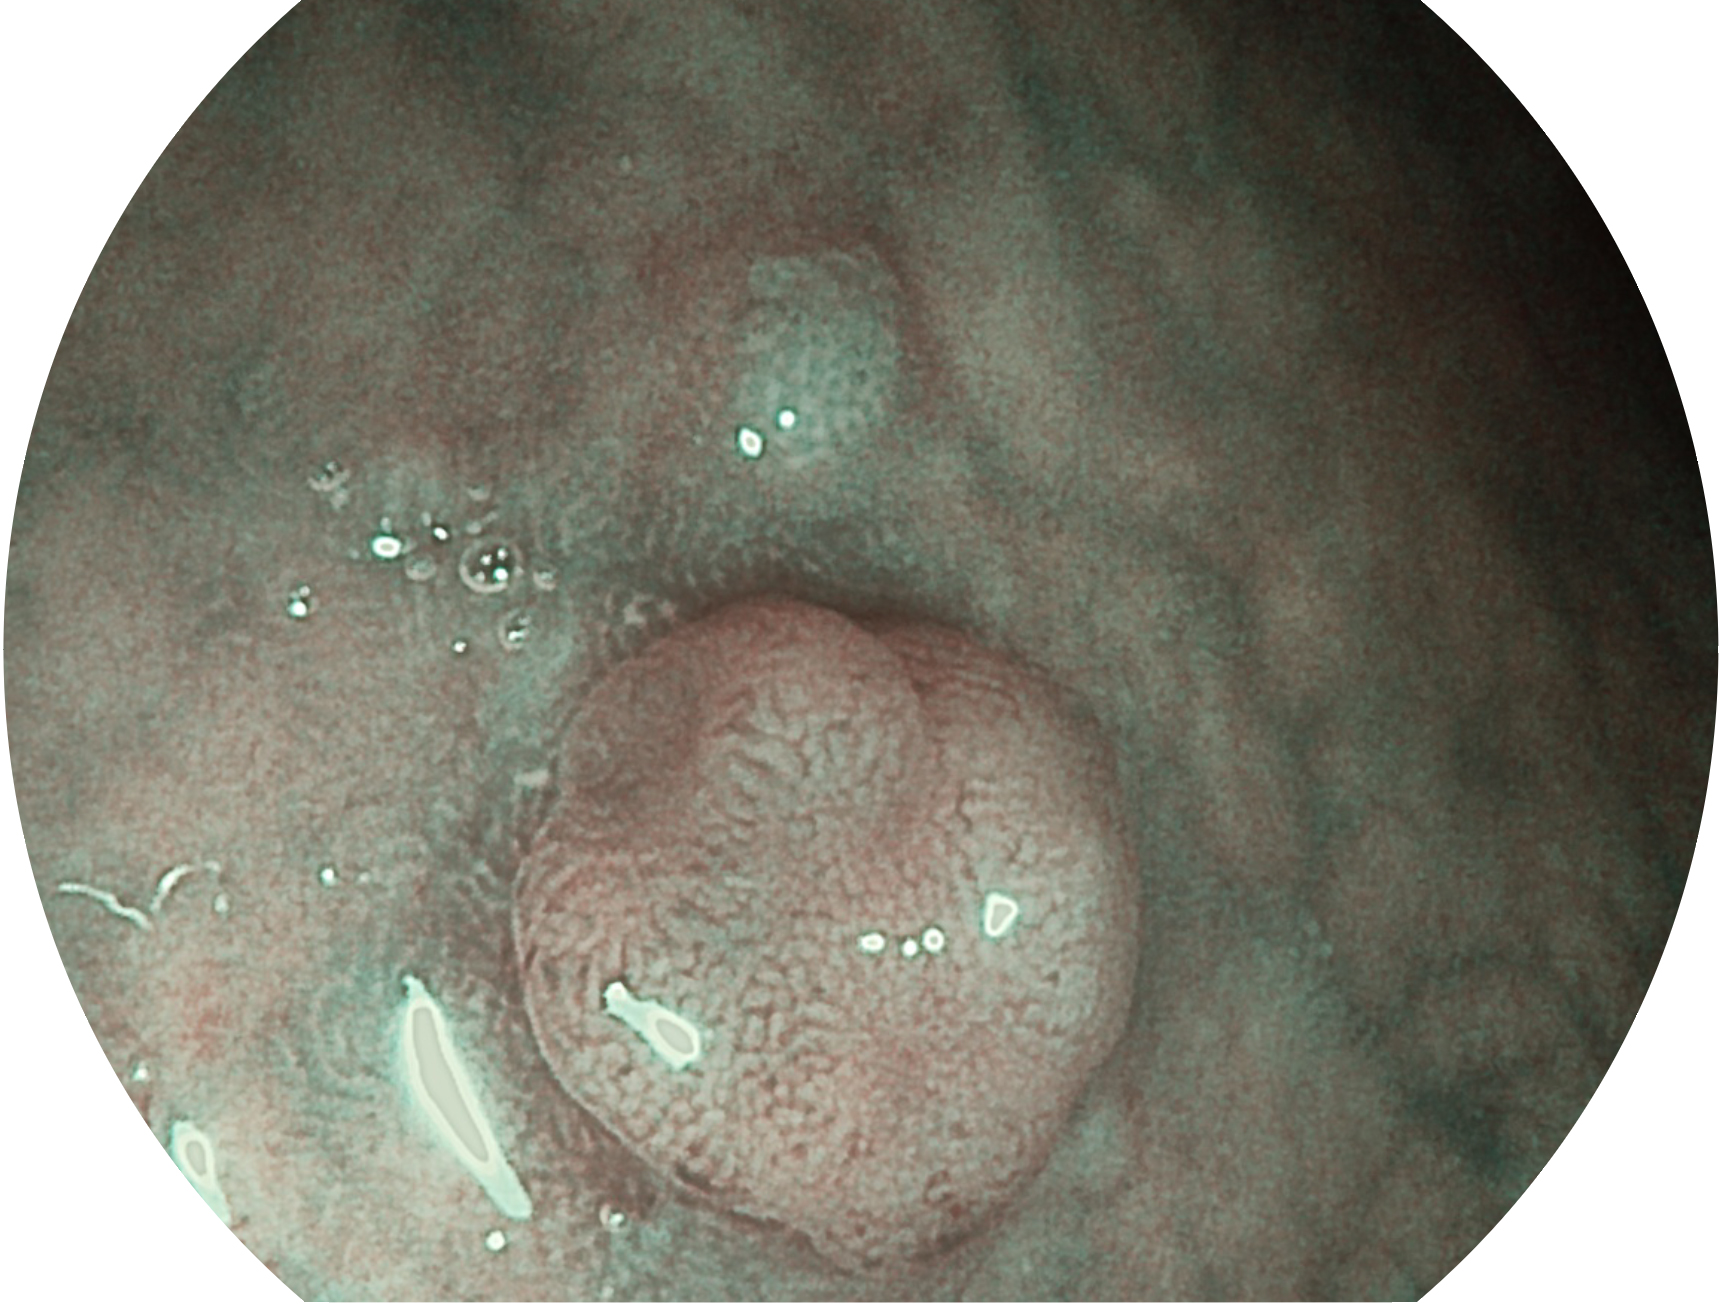

開立新開發(fā)的內(nèi)鏡染色技術(shù),主要是基于多波長(zhǎng)LED 光源的開發(fā),VLS-55Q 四波長(zhǎng)LED 光源是由四個(gè)不同顏色的LED光按照相應(yīng)照明模式所規(guī)定的特定發(fā)光比例進(jìn)行合束后形成,合束后形成的照明光的光譜由紅光、綠光、藍(lán)光及藍(lán)紫光這四個(gè)不同的波段范圍構(gòu)成。具有更高光譜自由度,通過光譜比例的控制,實(shí)現(xiàn)了聚譜成像技術(shù),英文全稱為“Spectral Focused Imaging, SFI”,縮寫為“SFI”和光電復(fù)合染色成像技術(shù),英文全稱為“Versatile Intelligent Staining Technology, VIST”,縮寫為“VIST”。